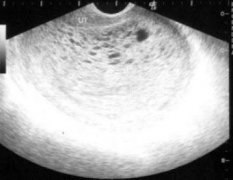

4、附件炎:女性生殖器官中输卵管和卵巢被称为子宫附件,附件炎是指输卵管和卵巢上出现的炎症,但输卵管卵巢炎常常合并有宫旁结缔组织炎和盆腔腹膜炎,且在诊断时也很难区分,这样宫旁结缔组织炎和盆腔腹膜炎就也被划入附件炎范围了。

5、盆腔炎:盆腔所指的范围包括子宫,两侧输卵管与卵巢以及支撑这些器官的附属组织。致病原因通常是病菌感染了内生殖器官。健康的女性自身都具有自然防御机制。通常情况下很少出现此病。